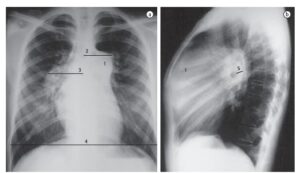

Hipofluxo pulmonar é a diminuição do fluxo sanguíneo nas artérias pulmonares, ou seja, menos sangue chega aos...

Hiperfluxo pulmonar é o aumento anormal do fluxo de sangue que passa pelas artérias pulmonares. Na radiografia,...

Hipertensão arterial pulmonar (HAP) é uma condição caracterizada pelo aumento anormal da pressão nas artérias pulmonares. Na...

Hipertensão venocapilar pulmonar é o aumento da pressão nas veias e capilares dos pulmões, geralmente como consequência...